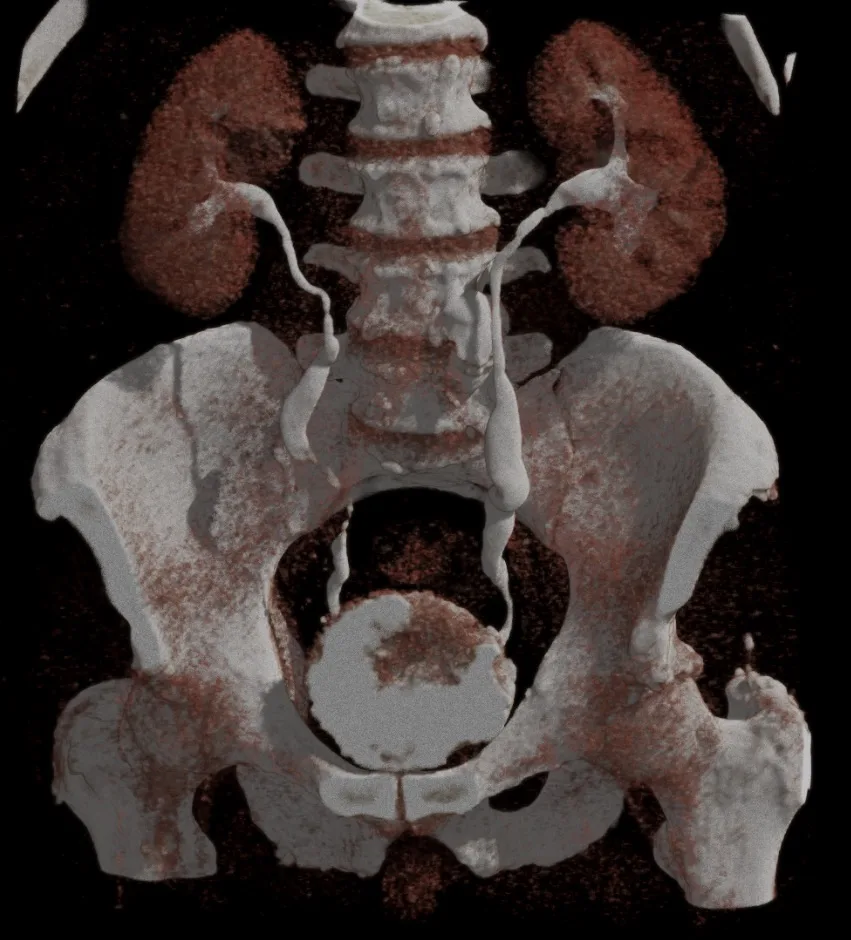

Пациент 27 лет. Две недели назад ударно-волновая литотрипсия. Неделю назад резкое повышение температуры тела, боли в боку. Повторная госпитализация. Установлен стент в левый мочеточник. Нарушения оттока мочи нет. На компьютерных томограммах левосторонний бактериальный нефрит, в верхнем полюсе левой почки – то, что иногда называют карбункул: воспалительный инфильтрат без формирования абсцесса (в англоязычной литературе называется нефрония). Принято решение продолжать антибиотикотерапию.